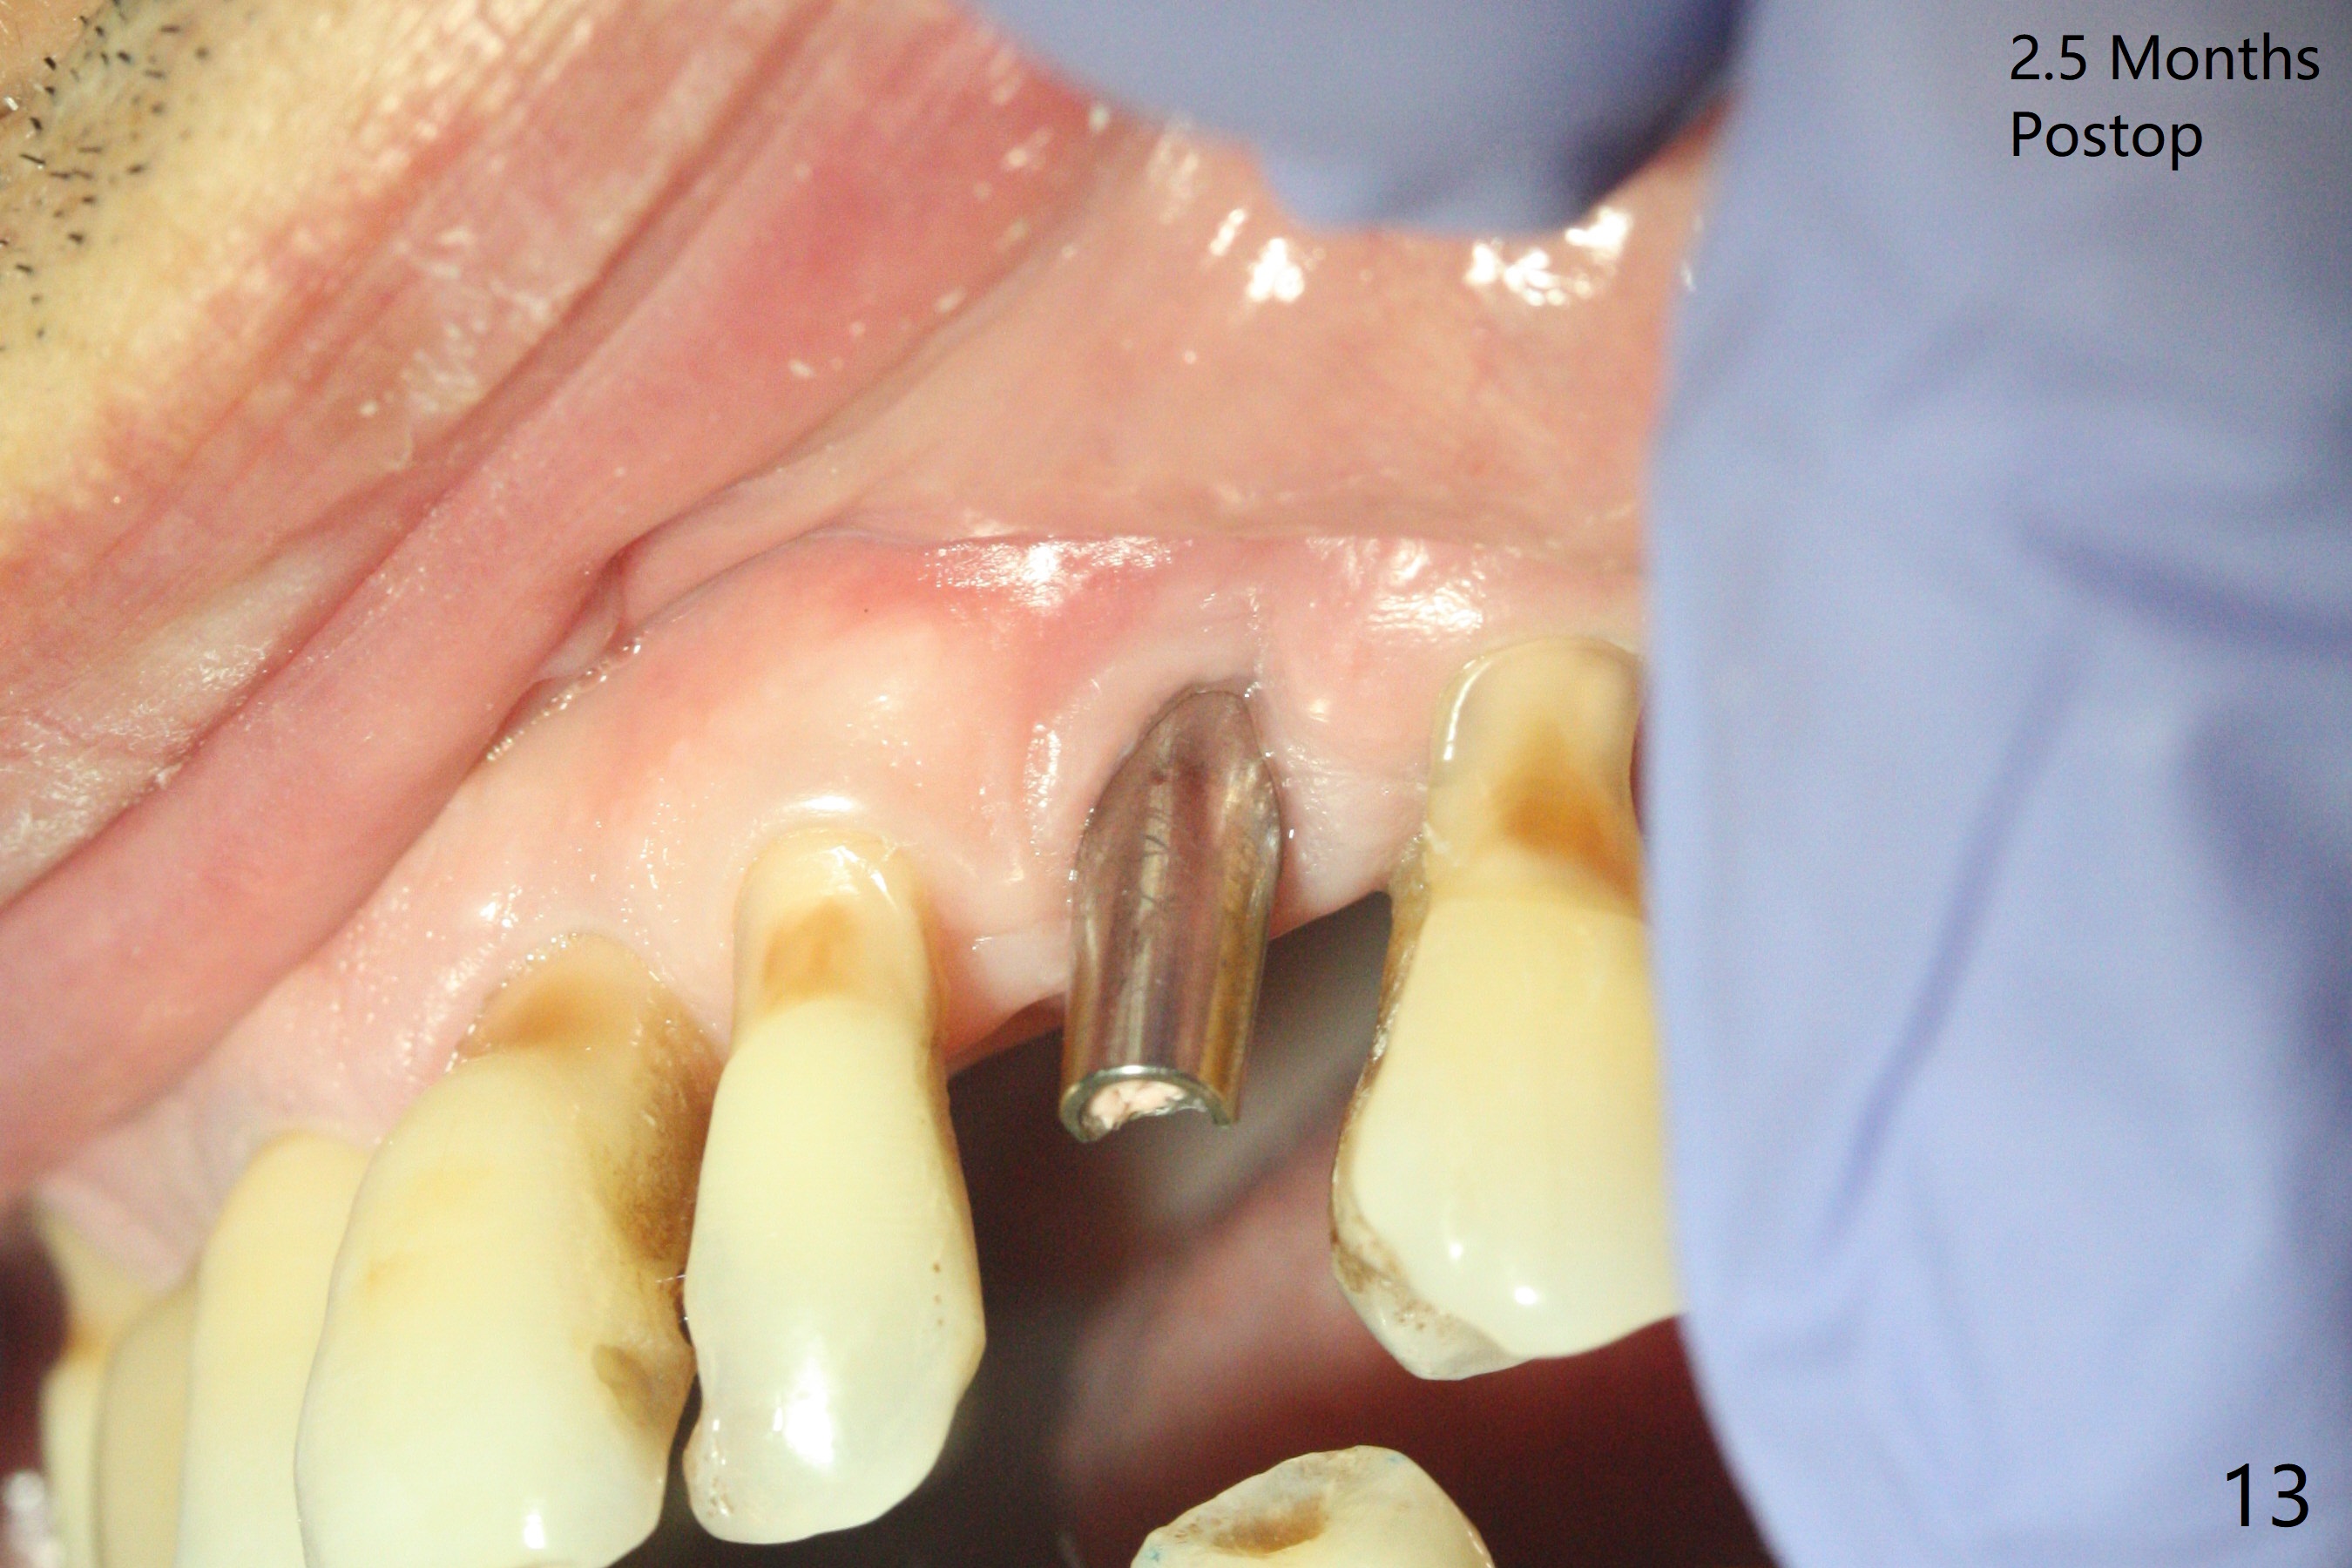

A 62-year-old man with generalized chronic periodontitis returns with chief complaint of loose tooth at #11 (Fig.1). Although a buccal fistula (Fig.1 <) is closer to #12 than to #11, percussion is more severe at #11 than 12. The buccal plate of #11 is missing, but it is possible to place a narrow immediate implant because of the wide alveolus (Fig.2). Since the gingiva is ~ 10 mm long, a mill abutment is to be used (Fig.3,5). In fact the fistula communicates with #11 extraction socket. After debridement, osteotomy is initiated (Fig.4) for a 3.8x10 mm implant ~ 35 Ncm, followed by seating a 4.5x2 mm mill abutment (Fig.5). Abundant sticky bone is placed in the remaining socket (for buccal plate reconstruction) and against the root surface of the neighboring teeth (Fig. 6 * (#10,12)). Finally 2 pieces of PRF membranes are utilized to facilitate repair of the buccal soft tissue defect (Fig.7 *). The root prominence of the canine seems to be maintained by the bone graft (Fig.8 C). Acrylic dressing holding the PRF membranes in place remains in situ with the healthy gingiva buccal (Fig.9) and palatal (Fig.10) 11 days postop. Note the acrylic locking into the undercuts of the neighboring teeth (*). 经过一段摸索发现离心每分钟1500转5分钟后,抽取上清液,接着再离心10分钟剩余上清液就形成血小板块,压制后便是血小板膜,后者似乎有助于软组织愈合,而上清液用来制备骨块,帮助硬组织生长。利用这个原则讨论以下病例治疗。The gingival margin gains ~ 5 mm 6 weeks postop when the acrylic dressing is removed (Fig.11,12 (<: previous one), as compared to Fig.7,8). 治疗结束时尖牙牙龈缘高于第一双尖牙(图七,八),六个星期后,尖牙牙龈缘却低于双尖牙(图十一,十二(箭头:原始牙龈缘))。术后2.5,4.5月基台周围牙龈似乎能与钛合金附着,防止细菌进入深部植体(图十三,十四)。临时牙冠脱落多次,可能与mill abutment太光滑有关,所以颊侧,舌侧磨成平面(图十四)。取模时好像不必取出基台清洗(仿佛没有炎症),原位用树脂延长基台。术后5个月CT显示颊侧骨板再生(图十六-十八)。取模时并没有用树脂加长基台;粘固时,牙冠颜色理想,但是照片中并不是如此(图十九,二十),颊侧骨板没有塌陷。术后11个月基台颊侧骨板没有萎缩(图二十一:B);3d图像:骨壁完全形成(图十六对比:部分形成)。密度也增高(图二十二:B),与术后五个月比较(图十七)。术后十一个月,粘固后五个月角化龈存在(图二十三),牙冠颈部有金属颜色透出,是因为二段式基台太粗了(最细4.5毫米),可以请实验室在牙冠内部涂opaque material而减轻。